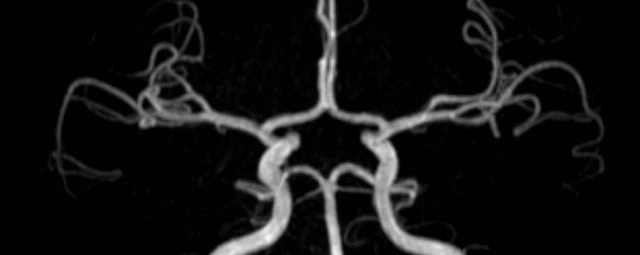

- MR-Angiografie ohne Kontrastmittel

- Time of Flight (TOF)-Angiographie

- Phasenkontrastangiographie (PCA). Geeignet zur Quantifizierung Stenose-/Insuffizienzgrad z.B. bei Herzklappen, falls echokardiographisch die Untersuchungsbedingungen eingeschränkt sind.

Je nach Fragestellung und Körperregion Gefäßdarstellung ohne Kontrastmittel bei Kontrastmittelunverträglichkeit oder terminaler Niereninsuffizienz möglich.

- MR-Angiographie mit Kontrastmittel

- Erfassung arterieller und venöser Gefäße/Bypässe aller Körperregionen mit 3D-Rekonstruktion

- je nach klinischer Fragestellung zeitaufgelöste MR-Angiographie (4D-MRA) z.B. bei Frage arteriovenöse Fistel/ Shunt oder Darstellung Unterschenkelarterien vor geplanter Bypassoperation.

Durchführung dieser Untersuchung nur an den Standorten am Diakonissenkrankenhaus und am Markkleeberg-Center